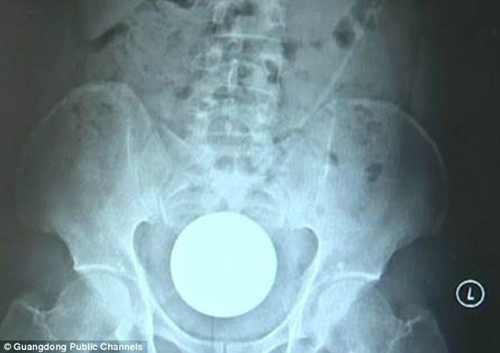

Phim chụp X-quang cho thấy quả bóng kích thước "khủng" nằm sâu trong trực tràng của bệnh nhân. |

Người đàn ông có tên Xiao Ming, 31 tuổi, đã phải đến bệnh viện ở Đông Quan, tỉnh Quảng Đông, Trung Quốc, cấp cứu do bị đau bụng dữ dội. Phim X-quang cho thấy có một vật thể hình tròn khổng lồ bị mắc kẹt trong trực tràng của anh ta.

Bác sĩ Ye giải thích rằng quả bóng quá lớn nên bệnh nhân không thể tự lấy ra được. Quả bóng thủy tinh được đo rộng 8 cm.